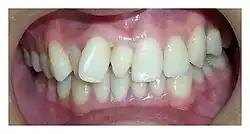

| Intraoral photograph showing conical mesiodens | |

- Conical (also called peg shaped);

The most common supernumerary tooth is a mesiodens, which is a malformed, peg-like tooth that occurs between the maxillary central incisors.